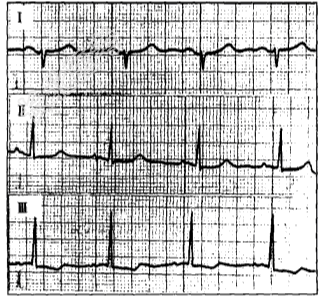

- 单项选择题患者,男, 68岁,肺动脉高压。心电图如图所示, 应诊断为

A、右心室肥大

B、后壁心肌梗死

C、不完全性右束支阻滞合并右心室肥大

D、不完全性右束支阻滞

E、完全性右束支阻滞